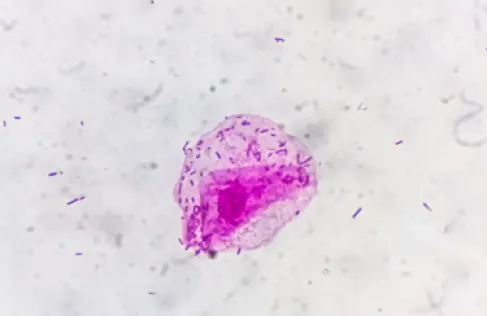

خبرني- أظهرت دراسة طبية حديثة أن ارتفاع مستويات الالتهاب المزمنة في الجسم قد يتسبب بإعتام عدسة العين أو cataract.

وأشار الباحثون إلى أن الالتهابات الجهازية هي عمليات التهابية طويلة الأمد، وغالبا ما تكون غير ملحوظة او لا تظهر لها أعراض واضحة، لكنها تتسبب بتلف بعض الأنسجة في الجسم تدريجيا، وقد يصل تأثيرها إلى عدسة العين، مما يساهم في تعتيمها، كما أن اختلال توازن العناصر الغذائية في الجسم، قد يلعب دروا مهما في هذا الأمر.